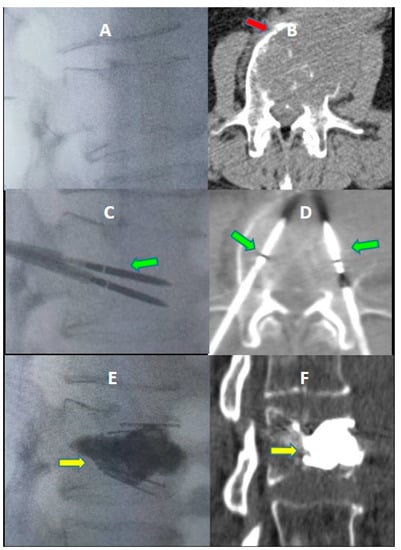

The details of the spine jack positioning procedure are described in Figure 2.

Figure 2. A 73-year-old male with a history of kidney cancer with lumbar pain. (A,B) Axial (A) and sagittal (B) CT scan showing metastatic lytic lesion of the L2 vertebra (white circle in (A,B)). (C) Axial CT image; two 10 Gauge beveled bone needles (Thiebaud Biomedical Devices) directly inserted into the posterior aspect of the vertebral body via a bilateral transpedicular approach (white arrows). (D) Axial CT image; first (right) microwave antenna inserted coaxially through the cannula for ablation (green arrow). (E) Axial CT image; second (left) microwave antenna inserted coaxially through the cannula for ablation (green arrow). (F) Axial CT image; after ablation, microwave needles were removed, and two blunt guidewires (red arrows) were inserted coaxially through the same access cannula. (G): Axial CT image; a designed drill (blue arrow) mounted on a working cannula was gently advanced coaxially into the left vertebral body until the desired position of the implant. Blunt guidewires (red arrows). (H) Axial CT image: after the removal of the left drill, an acrylic plug is left in place (orange arrow). Advancement of the drill to the right (blue arrow). Blunt guidewire (red arrow). (IL): Axial CT image; after preparation of both sides, two SpineJack® (yellow arrows) were inserted into the vertebral body through the working cannulae (I,J) and were gradually and simultaneously deployed (K,L). (M,N) Post-procedure control—CT in the axial (M) and sagittal (N) planes showed a correct expansion of the vertebra with a homogeneous distribution of the vertebral cement. No periprocedural complications were observed.